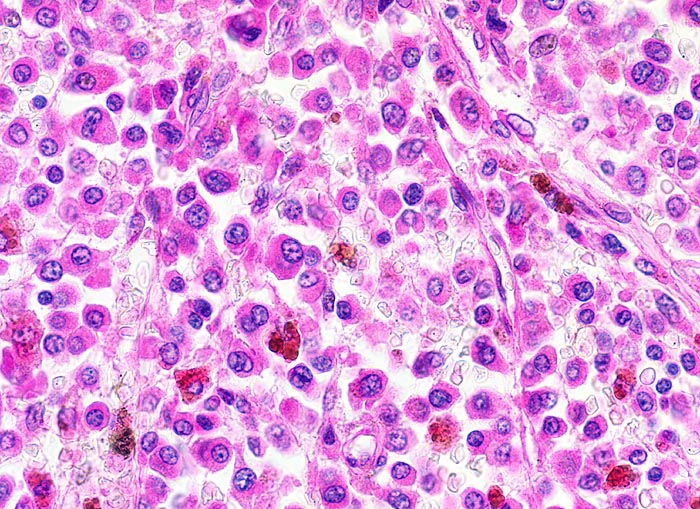

PathoPic – image database / PathoPic ID 4140 - Plasmazellmyelom

Plasmazellmyelom

maligner Tumor

Knochenmark, Wirbelkörper

Tumor ausschliesslich aus atypischen Plasmazellen zusammengesetzt: exzentrisch gelagerte Kerne, ausladendes Zytoplasma. Grobes, randständiges Heterochromatin, im typischen Fall mit Radspeichenstruktur.

Histologie

400